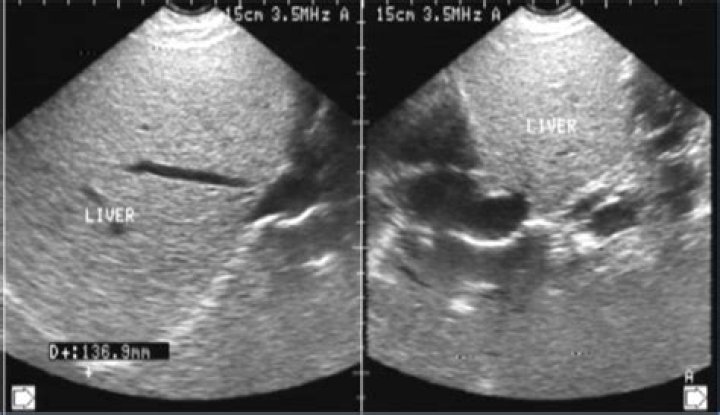

Altered parenchymal echotexture refers to changes in the normal appearance of an organ or tissue on an ultrasound examination, often indicating underlying...